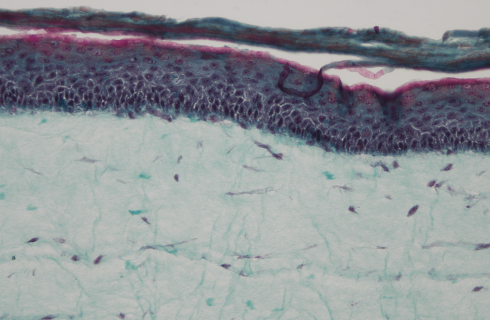

Upon arrival in Marseille, histology sections were obtained and microscopic examinations were done and analysed with Poietis‘ scoring grid (a tissue is considered compliant if its total score is ≥ 50%).

This revealed no statistical difference in appearance and scoring when compared to samples that were not transported.

Microscopy (X20) Histology Section

(GOLDNER TRICHROME STAINING)